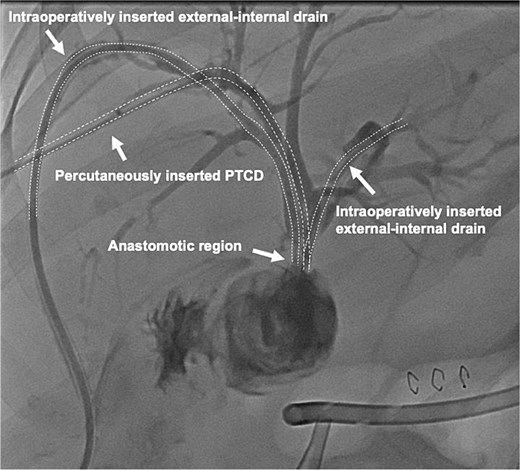

A 64-year-old obese woman presented to the emergency department with clinical signs of cholestasis. Initial imaging identified cholecystolithiasis and bile duct dilatation, later confirmed as choledocholithiasis visualized on endoscopic ultrasound. Subsequently, the patient underwent ERCP with papillotomy, stone removal and stent placement. Seven weeks later, an elective laparoscopic cholecystectomy was performed. Severe inflammation of the surrounding tissue was noted intraoperatively. The gallbladder was shrunken and embedded within the liver parenchyma, hindering the critical view of safety. On the first postoperative day, significant bile leakage of 400 ml was observed prompting an immediate exploratory laparoscopic revision by our hepatobiliary team. Here, a transection of the extrahepatic bile duct just above the hepatic duct confluence was detected, resulting in three separate ostia: two on the left side (left main duct and segment IV bile duct) and main right hepatic duct. To reconstruct the biliary anatomy the procedure was converted to open surgery. The two left-sided bile ducts were joined together by two interrupted stiches to create a common channel for the Roux-Y-hepaticojejunostomy. The right-sided duct required a separate HJ 3 cm proximally on the same jejunal limb. To prevent bile leakage and stenosis two external-internal biliary drains were placed in the left-sided anastomosis, routed transhepatically and ending in the jejunum (Fig. 1). Due to technical challenges related to the patient’s obesity a third external-internal biliary drain could not be placed in the right-sided HJ. The biliodigestive anastomosis was constructed with an interrupted absorbable 5/0 monofil sutures in duct-to extra mucosal technique.

Conjunction of the left-sided bile ducts into a single hepaticojejunostomy. The right-sided duct required a separate hepaticojejunostomy using the same jejunal limb. To prevent complications, transhepatic external-internal biliary drains were placed in the left-sided anastomosis, extending into the jejunum.

Contrast-enhanced image of the intraoperatively inserted external-internal drains and the percutaneous transhepatic cholangiography drainage (PTCD) which was interventionally inserted into the right duct on postoperative day one.